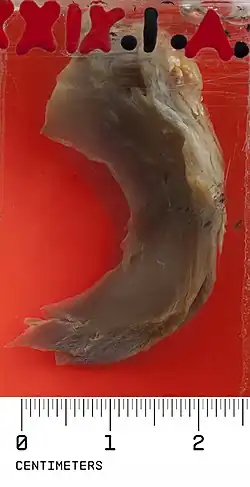

Normally, the meniscus is a thin crescent-shaped piece of cartilage that lies between the weight bearing joint surfaces of the femur and the tibia. It is attached to the lining of the knee joint along its periphery and serves to absorb about a third of the impact load that the joint cartilage surface sees and also provides some degree of stabilization for the knee. There are two menisci in the knee joint, with one on the outside (away from midline) being the lateral meniscus and the inner one (towards midline) the medial meniscus. A discoid meniscus is a congenital anomaly of the knee found in 3% of the population (up to 15% in Asia). It typically affects the lateral meniscus and may be found bilaterally (20%). Instead of the narrow crescent shape, as seen in a normal meniscus above, a discoid meniscus is thickened, and has a fuller crescent shape. In addition, a discoid meniscus does not taper as much towards the center of the joint and is shaped like a disc. The thickness of the meniscus, its diminished vascular blood supply, and in some instances, weak capsular attachment, makes it more prone to tears compared to a normal meniscus. The anomaly in itself is asymptomatic; however, a tear of the meniscus can result in pain, swelling, and snapping in the affected knee. The orthopedic classification of discoid menisci includes: complete, incomplete or Wrisberg-ligament types as depicted here. Coverage of the lateral tibial plateau determines the designation of complete or incomplete. The Wrisberg-ligament type has an abnormal posterior attachment by attaching to part of the posterior cruciate ligament.

In a patient complaining of acute onset knee pain, an X-ray study would be done to rule out any bony pathology such as a fracture. Since it is difficult to diagnose meniscal anomalies with X-ray, an MRI would be necessary to visualize the discoid meniscus. If the patient is asymptomatic and does not complain of significant locking sensation in the knee or pain, treatment is conservative and consists of stretching and strengthening exercises for the quadriceps and hamstring muscles. “In cases where there is significant disability, surgical excision may be needed. When the discoid meniscus is severely damaged, total excision of the meniscus may be necessary. In most cases where the meniscus is still generally intact, a partial excision to preserve the cushioning function may be sufficient.”[3]